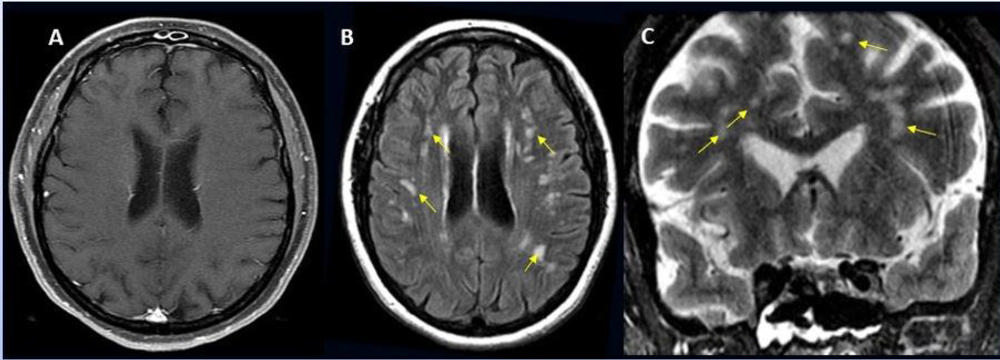

Figure 8. 65-year-old male smoker, presented with acute hypoxic respiratory failure secondary to COVID-19 pneumonia, requiring intubation. Hospitalization was complicated by seizures relating to cerebral edema and hemorrhagic posterior reversible encephalopathy syndrome.